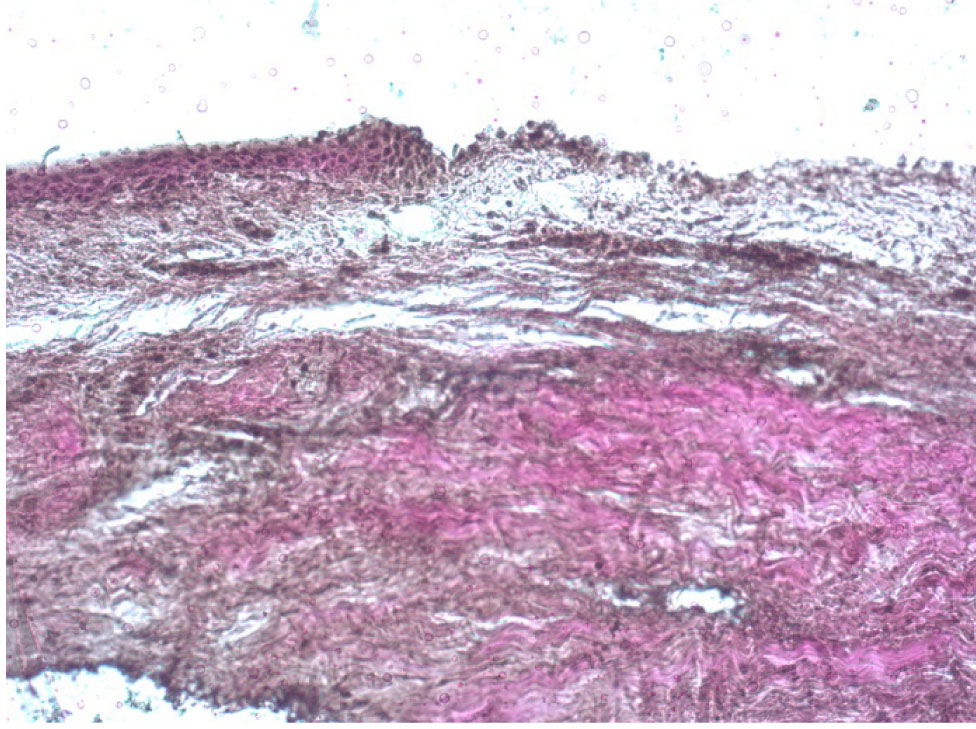

Во второй группе, где проводилась ограниченная по диаметру эксимерлазерная деэпителизация на глубину ⅔ эпителиального слоя с последующим механическим удалением оставшейся ⅓ эпителия, визуализировались как деэпителизированные участки, так и зоны с сохраненным эпителием, где определялась слоистость его строения от рядов кубических до плоских клеток без элементов ороговения (рис. 6). При окраске по Ван Гизону видно, что такие участки деэпителизации дали возможность пройти раствору рибофлавина в строму роговицы на всю ее глубину, что отразилось в появлении лакунарных пространств на всей площади поперечного среза роговицы до десцеметовой мембраны. Коллагеновые волокна при этом сохранили однонаправленность ориентации параллельно поверхности роговицы.

Наибольшее разрыхление передней стромы роговицы отмечалось в проекции зоны деэпителизации. Однако аналогичная картина с появлением большого количества лакунарных пространств между волокнами коллагена наблюдалась и под сохраненным эпителием, что говорит о наличии межламеллярного распространения раствора рибофлавина на область, превышающую по размерам зону деэпителизации, что подтверждает целесообразность проведения деэпителизации только в зоне кератоконуса и осуществления ультафиолетового облучения как в зоне полной деэпителизации, так и перифокально с захватом роговицы с сохранным эпителием.